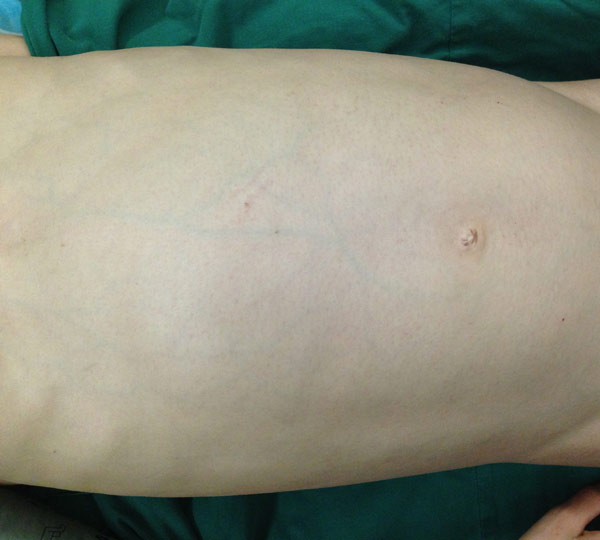

从外形上看,小黄瘦小的身躯大腹便便,貌似怀孕许久,与她年幼的面庞极不相乘。近日,小黄接受了手术治疗,医生成功为其切除了一个约7公斤的肿瘤,解除了伴随十年的“包袱”,术后经病理证实,小黄肚中包块为未成熟性畸胎瘤。

小黄肚大似有孕

术后重现平坦腹部